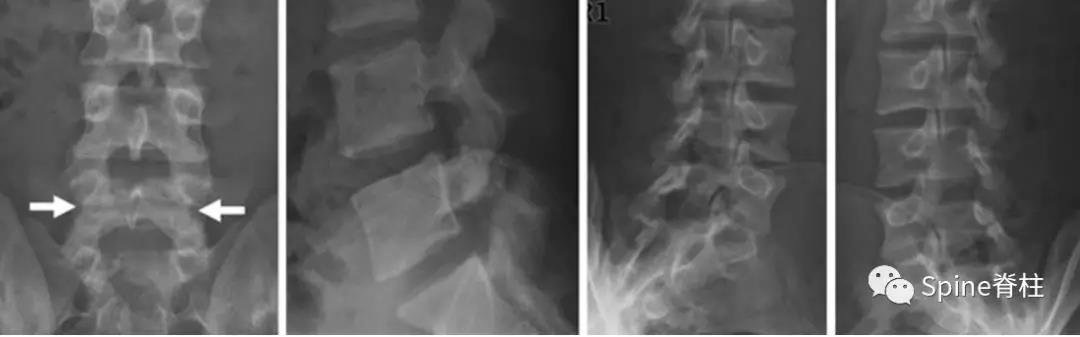

图:L5全椎板裂15岁相扑运动员,严重腰痛,后伸明显加重正侧位X线示椎板水平骨折线(白箭头)。MRI示T2椎板高信号,T1椎板低信号